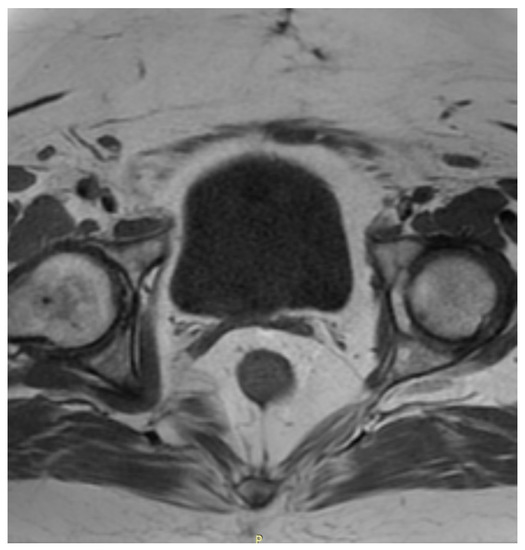

Three months after the initial hospitalization, the patient was admitted to the onco-logical gynecological ward. On admission she presented no irregularities in gynecological examination. A transvaginal ultrasonography of the uterus and pelvis was performed and a myoma, ca. 5 cm in diameter was found in the uterus wall. No other lesions were identified. A preoperative MRI of the abdomen and pelvis allowed identification of another 4 myomas in the uterus, with sizes from 7 to 54 mm, as shown in Figure 2.

Additionally, in the posterior wall of the cervix an irregular area (14 mm × 25 mm × 9 mm) was found, which was probably a malignant lesion. A single lymphatic node in the right inguinal area, with a diameter of 10 mm, was also identified. Remembering her symptoms and a history of a neoplasm in her family, the patient demonstrated a high level of anxiety towards her neoplasm. She expressed a wish to implement a radical treatment to ensure a disease-free result and this was also taken under consideration while choosing the therapeutic path.

Figure 2. A preoperative MRI of the pelvis in (A) axial and (B) sagittal projection. Both show the presence of myomas in the uterus. Arrows show myomas in the uterus.